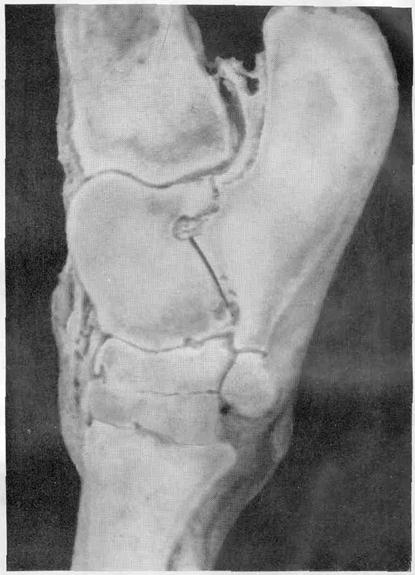

Рентгеновские снимки анкилоза суставов: Как это выглядит